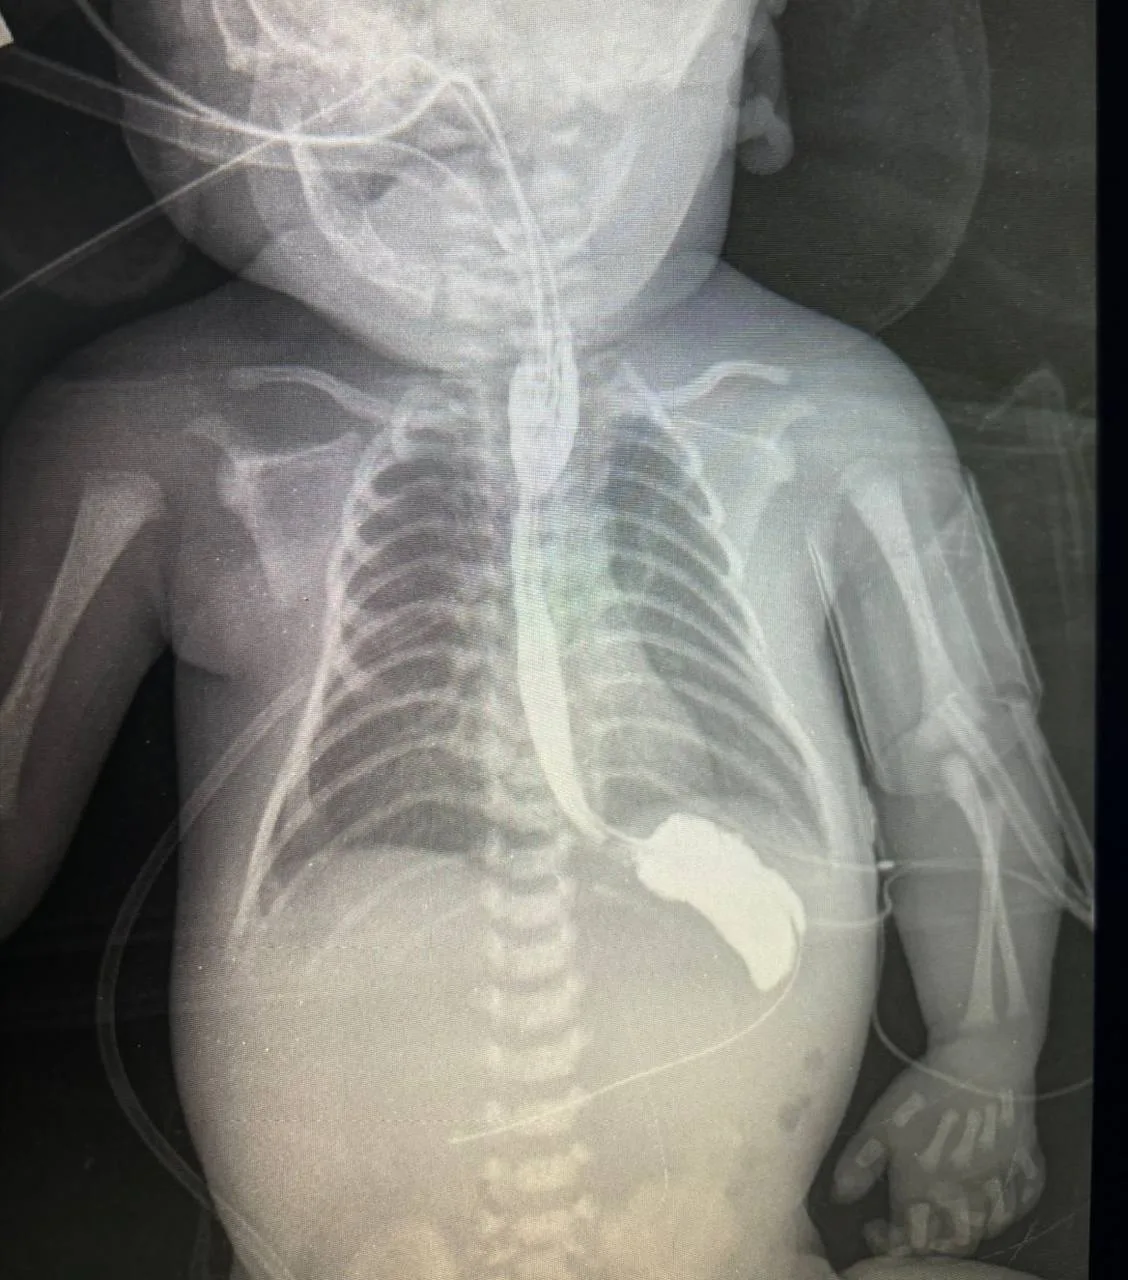

В Московском областном центре охраны материнства и детства городского округа Люберцы спасли новорожденного мальчика с патологией пищевода.

Неполное его развитие не дает возможности кормления ребенка. Но это лишь одна из опасностей заболевания. В большинстве случаев ниже зоны слепого конца пищевода формируется свищ, маленькое соустье, которое соединяет пищевод и трахею. Наличие такого свища опасно постоянным попаданием слюны из пищеварительного тракта в трахею, что быстро приводит к развитию тяжелых форм пневмонии.

Статистика говорит, что атрезия пищевода встречается только у одного из 5-6 тысяч новорожденных, для специалистов МОЦОМД это не редкий случай, хирурги проводят подобные операции ежемесячно. Подмосковье занимает третье место в России по числу прооперированных детей с данной патологией.